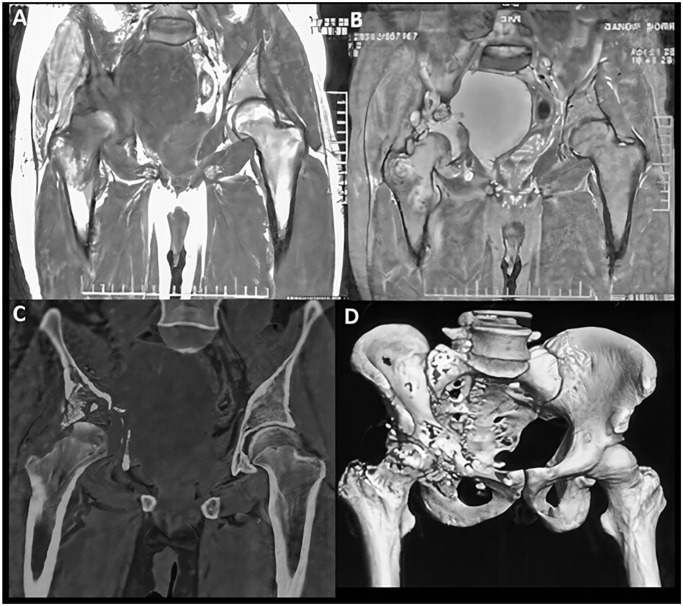

盆腔肿块伴有模糊症状的疑似病例应考虑囊性棘球蚴病的鉴别诊断。原发性盆腔包虫囊肿非常罕见,早期诊断非常重要,因为累及盆腔骨骼的包虫囊肿很难治疗,而且复发的可能性更大。本病例报告介绍了一例罕见的原发性盆腔包虫囊肿病例,患者为一名 30 多岁的男性。患者有排尿困难和慢性盆腔疼痛的模糊症状。一线放射成像技术诊断为肿瘤性肿块和结核病,而核磁共振成像显示为囊性疾病,可能是包虫囊肿。手术切除和组织病理学检查证实了原发性盆腔包虫囊肿的诊断。了解囊性棘球蚴病的各种表现有助于获得准确诊断,从而减少与该病相关的严重并发症。本病例报告强调了在盆腔囊性肿块的鉴别诊断中考虑寄生虫感染的重要性,即使在寄生虫流行率较低的地区也是如此。

The differential diagnosis of cystic echinococcosis should be considered in the suspected case of a pelvic mass presenting with vague symptoms. Primary pelvic hydatid cyst is rare, and the achievement of early diagnosis is important, as the involvement of bone in the pelvis is difficult to treat, and the probability of recurrences is greater. This case report presents a rare case of a primary pelvic hydatid cyst in a male in his 30s. The patient presented vague symptoms of difficulty in micturition and chronic pelvic pain. First-line radiological imaging techniques diagnosed it as a neoplastic mass and tuberculosis, while MRI revealed it as a cystic disease, probably a hydatid cyst. Surgical excision and histopathological examination confirmed the diagnosis of a primary pelvic hydatid cyst. Acquaintance with the varied presentation of cystic echinococcosis helps to obtain an accurate diagnosis and thus decreases the severe complication associated with the disease. This case report highlights the importance of considering parasitic infections in the differential diagnosis of cystic pelvic masses, even in regions with low endemicity.